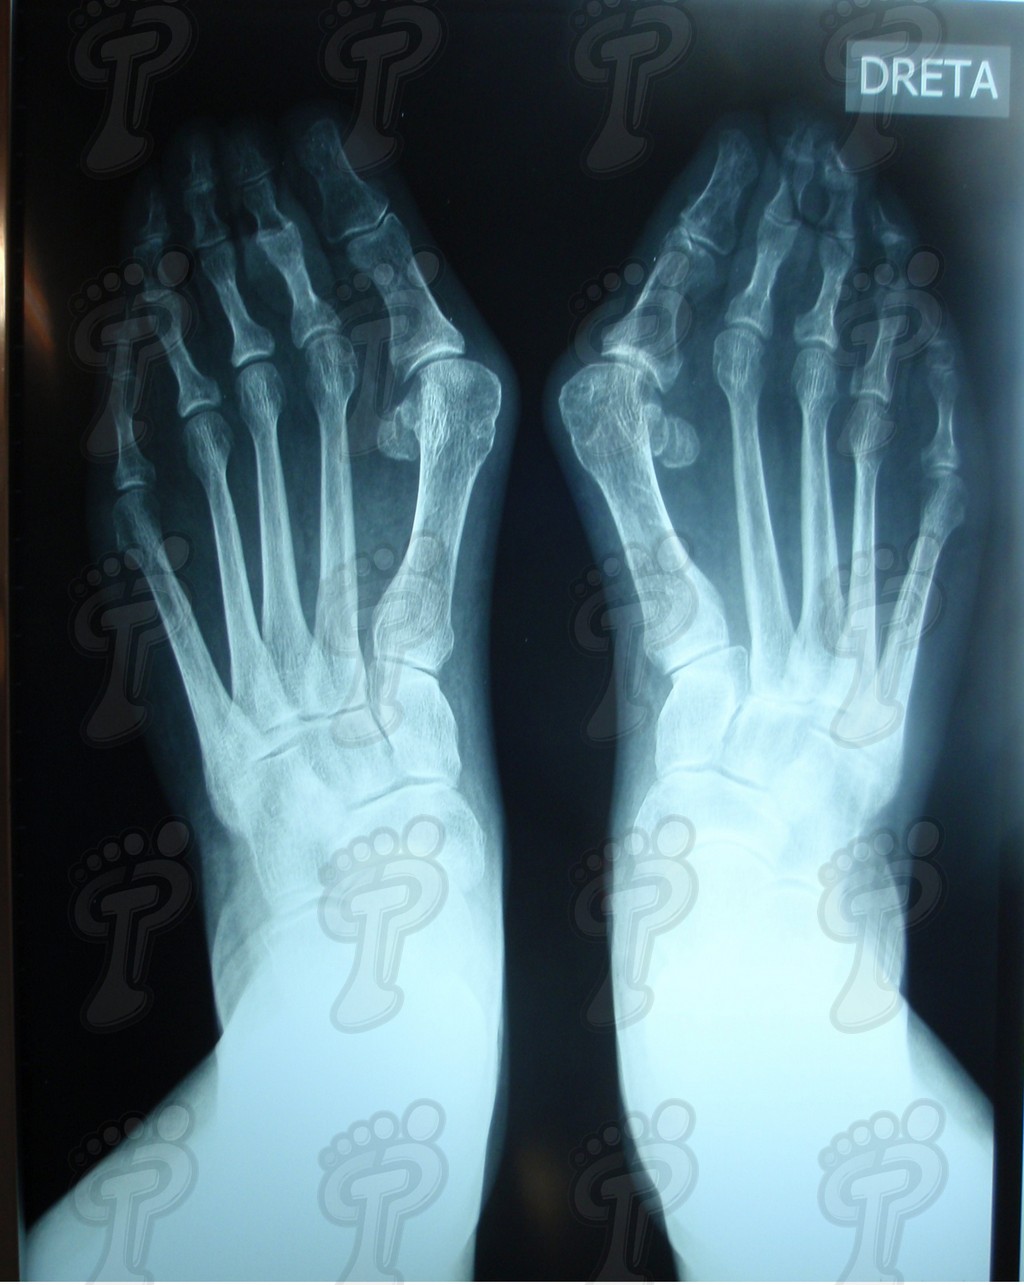

Imagen radiológica de hallux valgus.